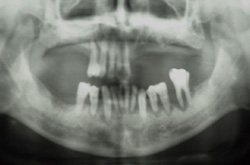

![]() 装着状態( *X 線写真の筋状の透過像は現像器によるもの) |

| 全体像;上顎も骨吸収に合わせた植立(修復材料は金白金系合金+ハイブリッドレジン) | |

装着状態( *X 線写真の筋状の透過像は現像器によるもの)